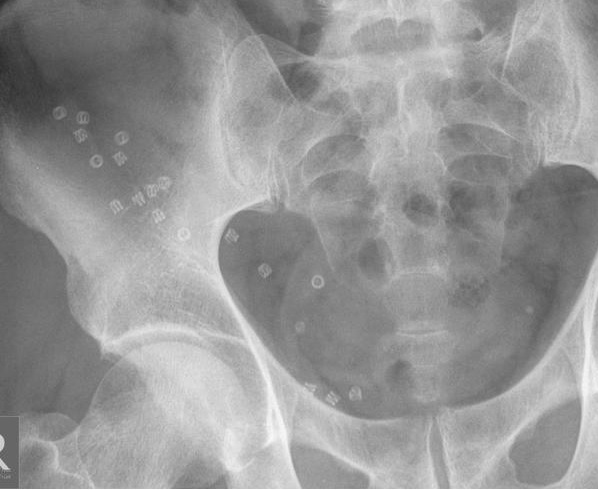

ظهر بالأشعة عدم وجود كسر. لكن أظهرت الأشعة

وجود أجسام غريبة معدنية ناحية أسفل يمين الصورة.

لم يمكن نسخ صورة الأشعة الأصلية لكنها كانت مماثلة

للأشعة التالية (صورة أشعة مفتوجة المصدر من موقع راديوبيديا)

طبعاً لقد إستبعدنا وجود كسر بالأشعة وتحقق

الغرض منها. ولكن ظهرت إشكالية جديدة قد تسمى في عرف طب الأشعة Incidentaloma بسبب العثور على شئ غير يتوقع وغير معروف

ماهيته.

وهو الأجسام المعدنية؟ وتم التأكد من أن

المريض وملابسه ليس بها شئ. ولا يبدو أنها أشياء مبتلعة بالجهاز الهضمي.

في هذه الحالة إجتهدت مع زميلي د محمد

عمروسي في التخمين. فهذه "الأشياء" تبدو معدنية وتشبه السوستة/الزنبرك

ومكانها مجمعها حول المنطقة الإربية. فربما كانت نوع ما من دبابيس تثبيت عمليات

الفتق مثلا.

فبحثنا على الإنترنت عن دبابيس تثبيت جراحي

لولبية فعثرنا عليها وعثرنا على الصورة النادرة المماثلة لحالتنا المرفقة في هذه

المدونة.